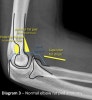

Anterior fat pad is located in the coronoid fossa. A narrow anterior fat pad is a normal finding on the lateral view.

The posterior fat pad is located in the olecranon fossa on the lateral view. It should not be visible under normal circumstances.

3) Supinator fat pad sign

Supinator fat pad can be raised or obliterated as a result of bony injury, particularly to the radial neck.

It is one of those unreliable soft tissue signs, but is useful as a guide to potential bony injury.